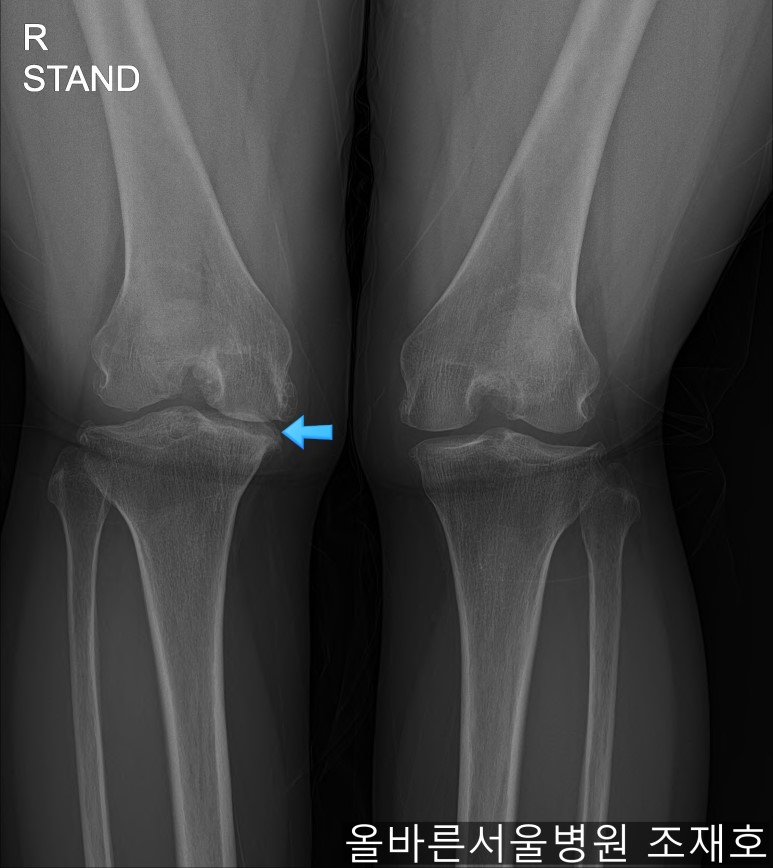

仅通过放射线片子观察到:右膝由于炎症严重,内侧胫骨及股骨已接触在一起,向内测严重变形。

左膝虽然也观察到了炎症,但远不如右膝严重。

如果通过X光片也观察到相同的病症,可以判断内侧关节的软骨大部分都损伤了。

观察膝盖下肢排列的扫描图像可看到右腿严重变形,身体中心向内倾斜。